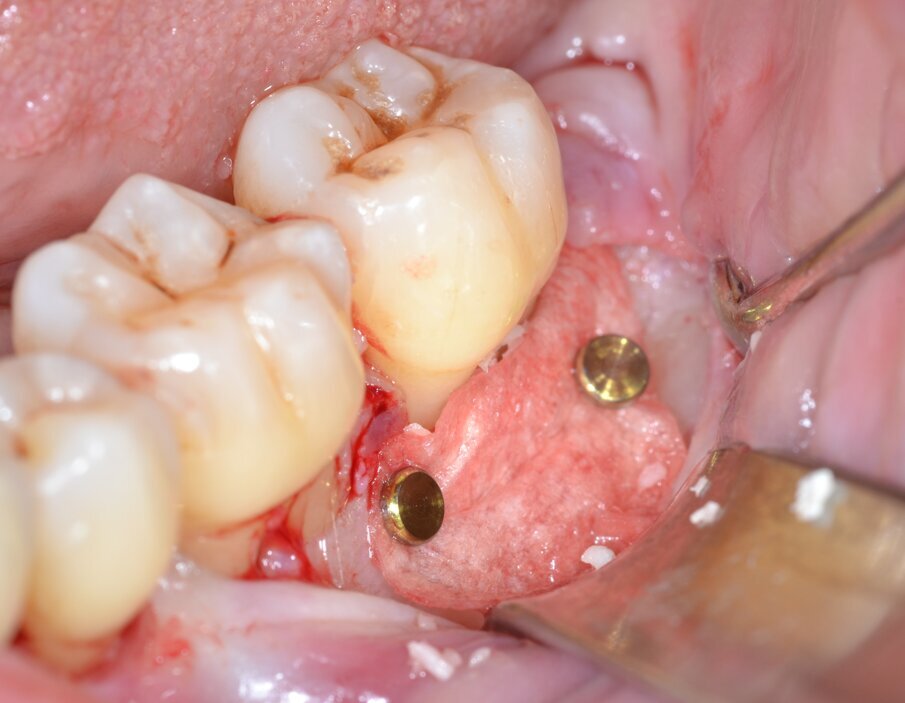

Dopo analgesia locale ottenuta per infiltrazione di Articaina cloridrato 40 mg con epinefrina 1:100.000 viene effettuata l’incisione di accesso secondo la tecnica denominata “Crestal Incision”4 per elevare un lembo a spessore totale che espone l’area interessata dal difetto (Fig. 5). Il debridement e la decontaminazione della superficie radicolare vengono effettuati per mezzo di inserti ultrasonici dedicati (Figg. 6, 7); al completamento di questo tempo chirurgico il difetto è innestato con biomateriale eterologo protetto da una membrana di tipo riassorbibile in pericardio di origine animale che viene fissata sulla cresta ossea mediante pins in titanio allo scopo di stabilizzare il coagulo e guidare la rigenerazione tissutale all’ interno del difetto. La ferita chirurgica è suturata con un filo riassorbibile 6/0 in PGA (Figg. 8-12).

Fig. 11 - Stabilizzazione della membrana barriera mediante pins in titanio.